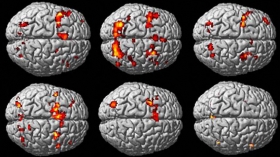

La imagen por resonancia magnética funcional (fMRI, por sus siglas en inglés) es el método más extendido para estudiar el esfuerzo que realiza una región determinada del cerebro cuando se le asigna una tarea. La fMRI detecta qué zonas están reclamando más energía del flujo sanguíneo gracias al oxígeno que transporta. El resultado son esos mapas en 3D de la materia gris con unas zonas iluminadas. Y los científicos nos dicen: esa es la parte de tu cabeza que se activa cuando comes chocolate, cuando piensas en Trump, cuando ves películas tristes, etc.

Ahora, un equipo de científicos liderados por Anders Eklund ha destapado que muchas de esas zonas se pudieron iluminar por error, por un fallo del software y el escaso rigor de algunos colegas. En su estudio, publicado en PNAS, cogieron 500 imágenes del cerebro en reposo, las que se usan como punto de partida para ver si a partir de ahí el cerebro hace algo. Usaron los programas más comunes para realizar tres millones de lecturas de esos cerebros en reposo. Esperaban un 5% de falsos positivos y en algunos casos dieron hasta con un 70% de situaciones en las que el programa iluminaba una región en la que no pasaba nada, dependiendo de los parámetros.

Estos programas dividen el cerebro humano en 100.000 voxels, que son como los píxeles de una foto en versión tridimensional. El software interpreta las indicaciones de la resonancia magnética e indica en cuáles habría actividad, a partir de un umbral que en muchos casos ha sido más laxo de lo que debiera, propiciando falsos positivos. Además, los autores de la revisión analizaron 241 estudios y descubrieron que en el 40% no se habían aplicado las correcciones de software necesarias para asegurarse, agravando el problema de los falsos positivos.